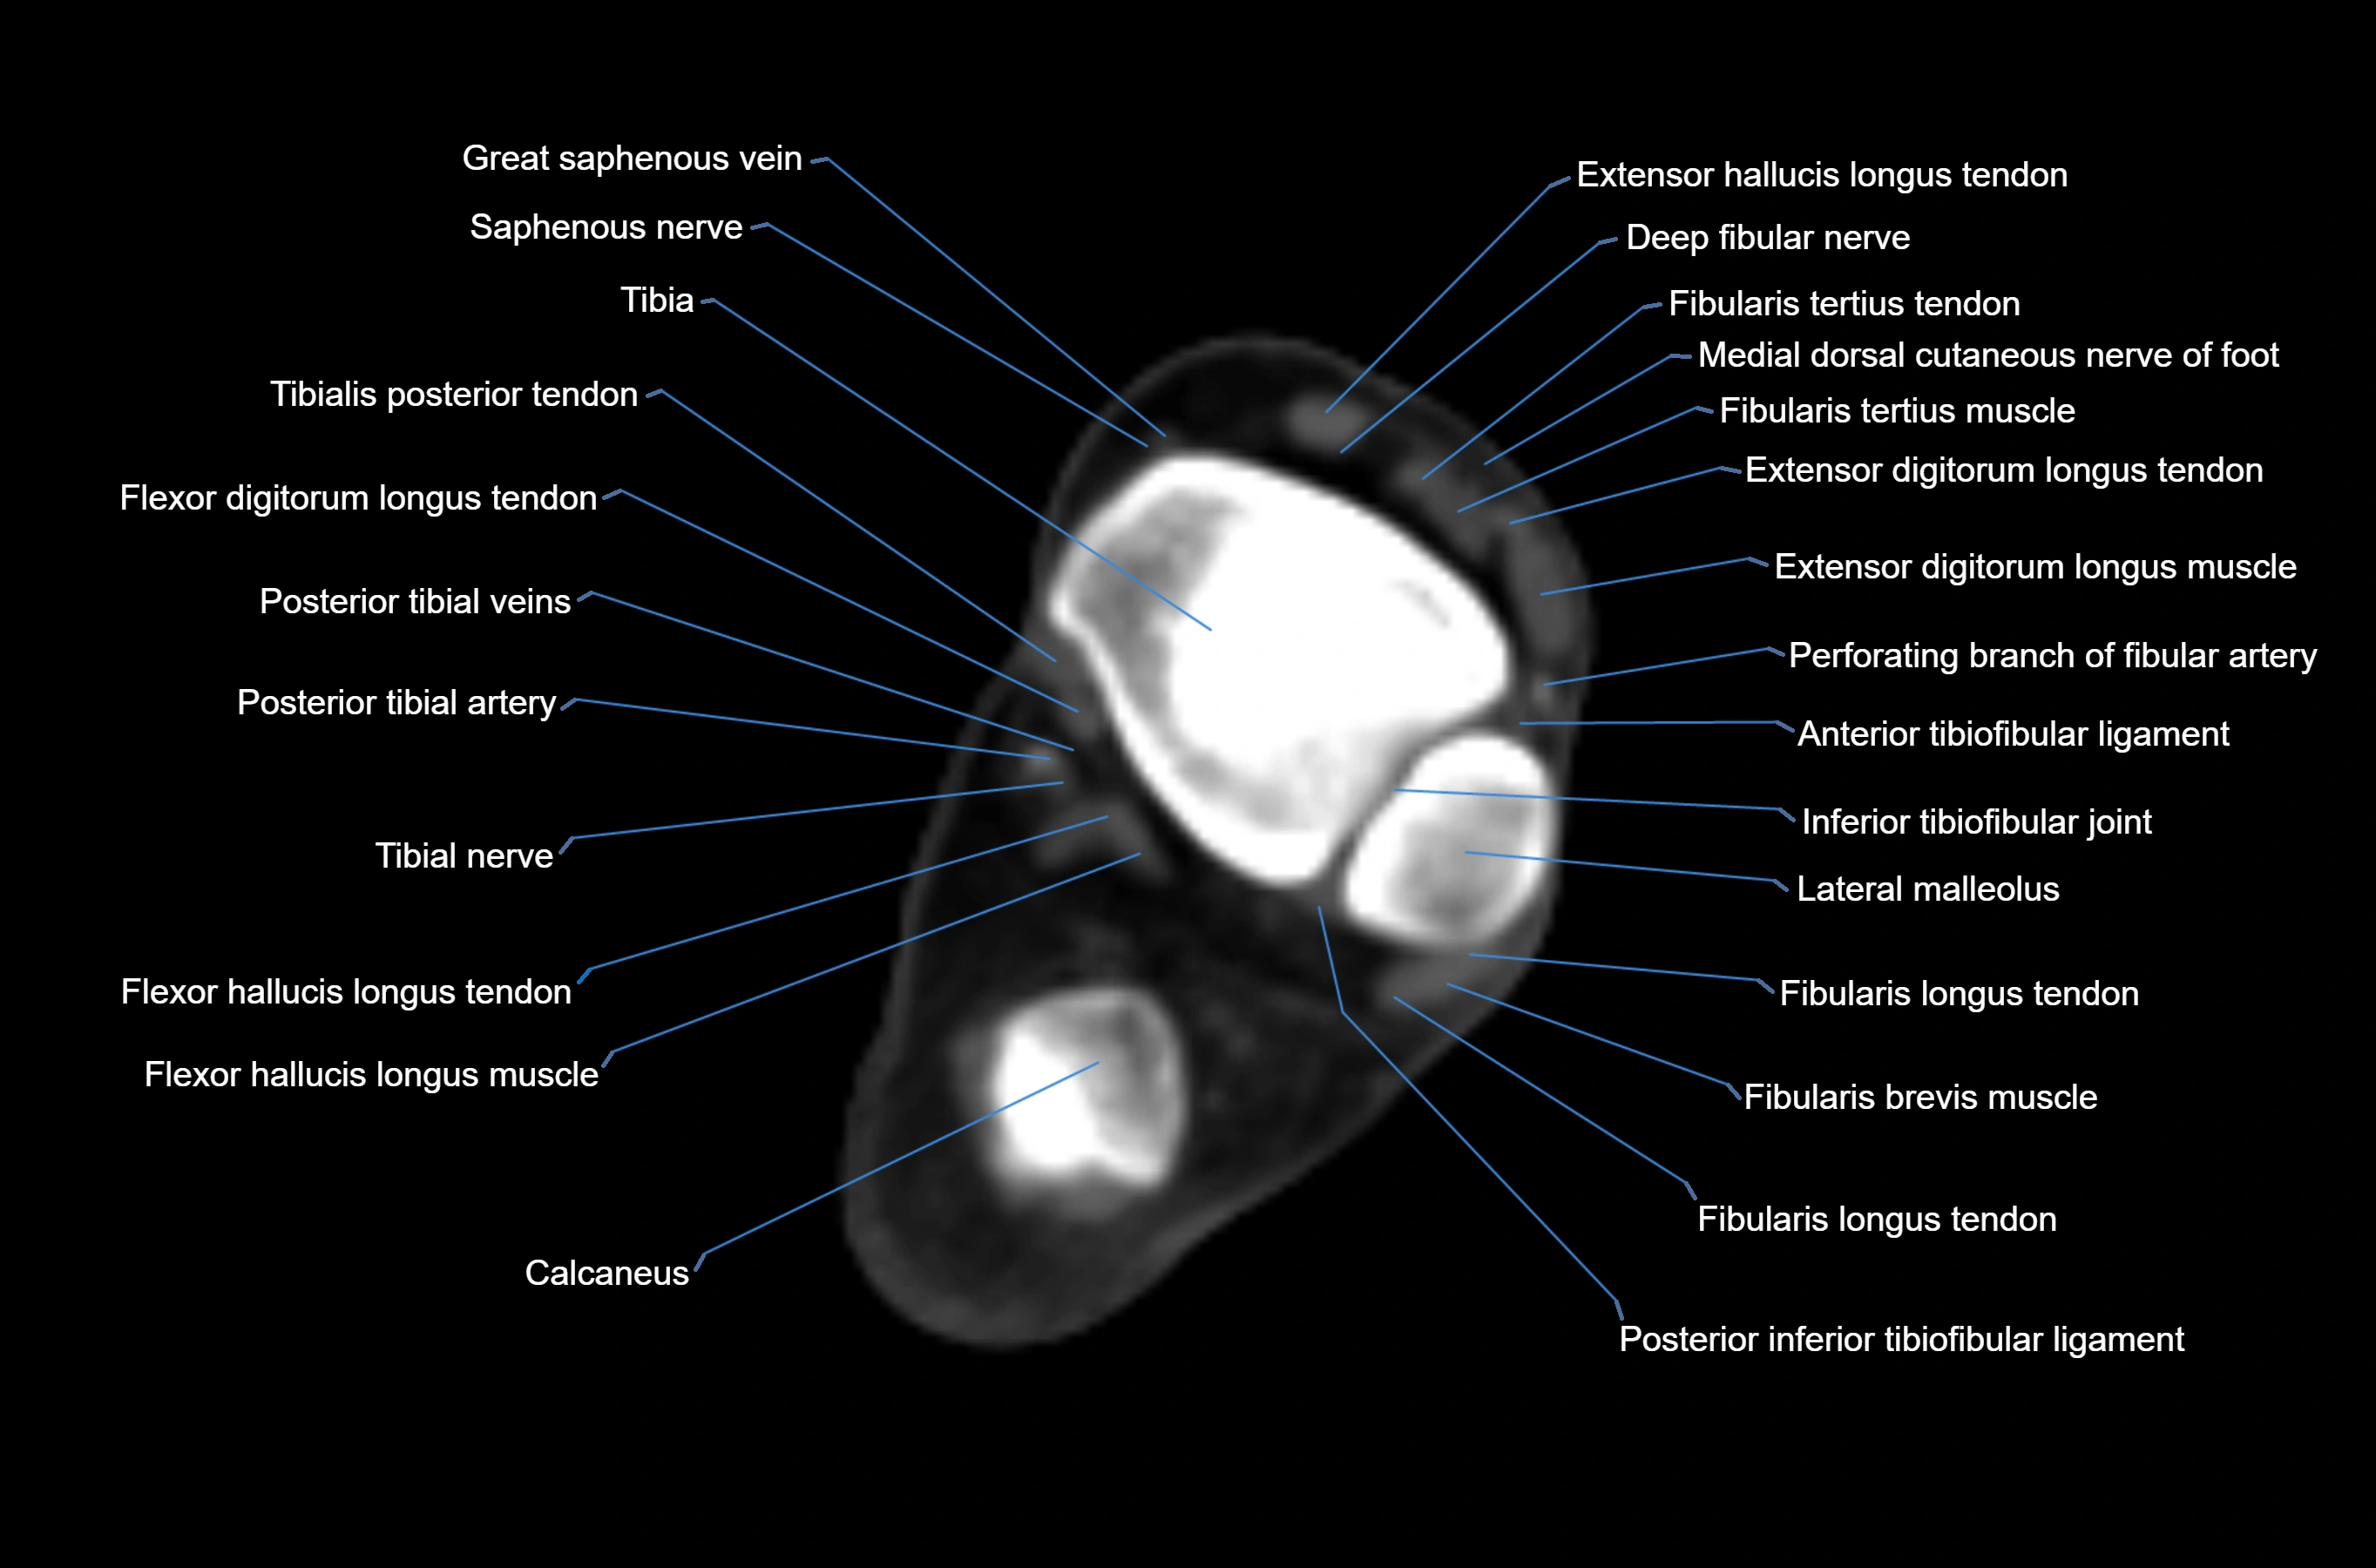

CT image